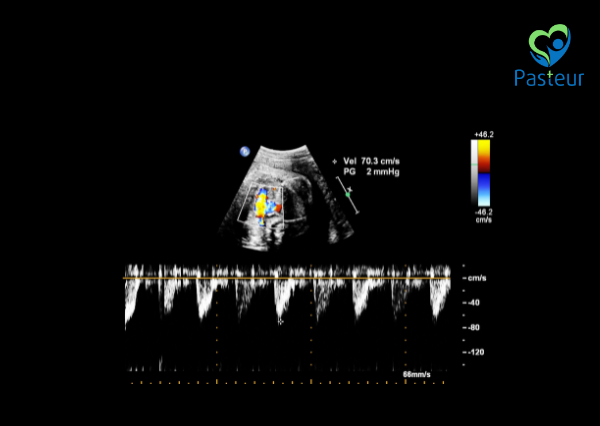

- Phân tích hình ảnh, đo lường chỉ số tim mạch và đánh giá dòng chảy qua van tim.

Tại Phòng khám Đa khoa Pasteur, siêu âm tim thai được thực hiện bởi đội ngũ bác sĩ giàu kinh nghiệm, sử dụng máy siêu âm 4D Doppler màu hiện đại, giúp đánh giá chính xác cấu trúc và chức năng tim thai. Các mẹ bầu cần tư vấn dịch vụ có thể liên hệ Tổng đài 0236 9999 868 hoặc tìm hiểu chi tiết dịch vụ khám thai đầy đủ tại đây